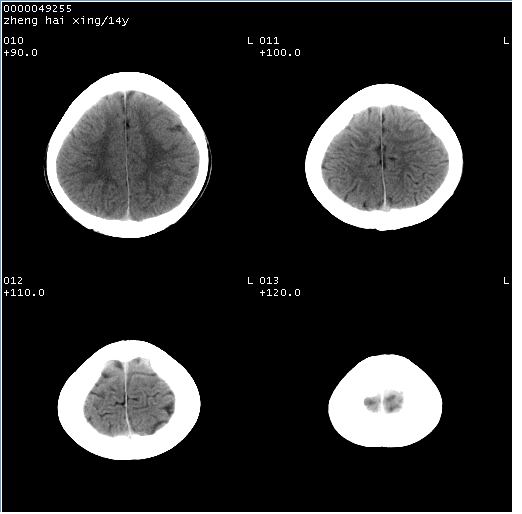

颅脑ct轴位平扫(层厚、层距均为10mm),图像如下:

双侧侧脑室之间无透明隔,双侧额角前方变扁,交角变钝。支持透明隔缺如!

透明隔缺如可为先天性缺如,亦可继发于因脑积水,脑室内压力增高,使其变薄,以至不能显示。一般无临床意义,但可并发于其他畸形或作为隔—视综合征的组成部分。

调一下窗寛窗位,或者透明隔太薄,容积效应而显示不好。